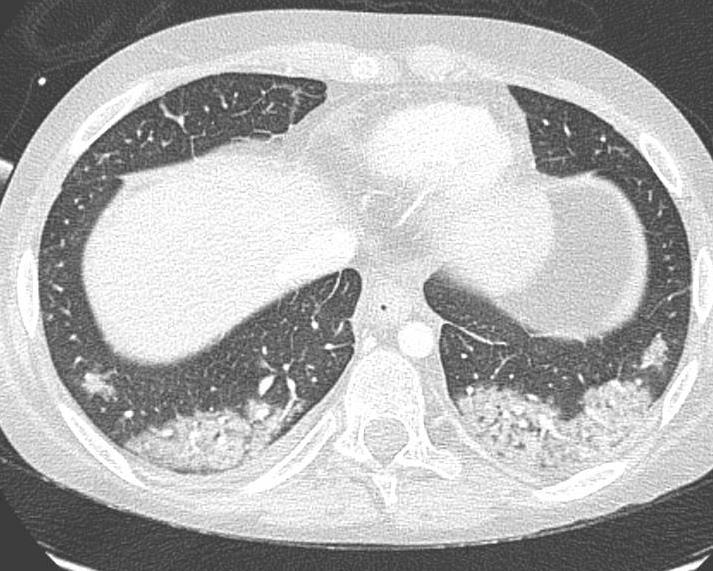

Acute Pediatric COVID-19: CT

21 Imaging of Covid 19 infection in children

Progressive: Diffuse GGO

Developed: Consolidation

• Patchy bilateral GGO, Consolidations or both

• Peripheral and lower lung zone predominance

• Bilateral & multifocal GGO, +/Consolidations or both

• Halo sign

• Peripheral and subpleural

Imaging of Covid 19 infection in children COVID 19 Late

Late

37